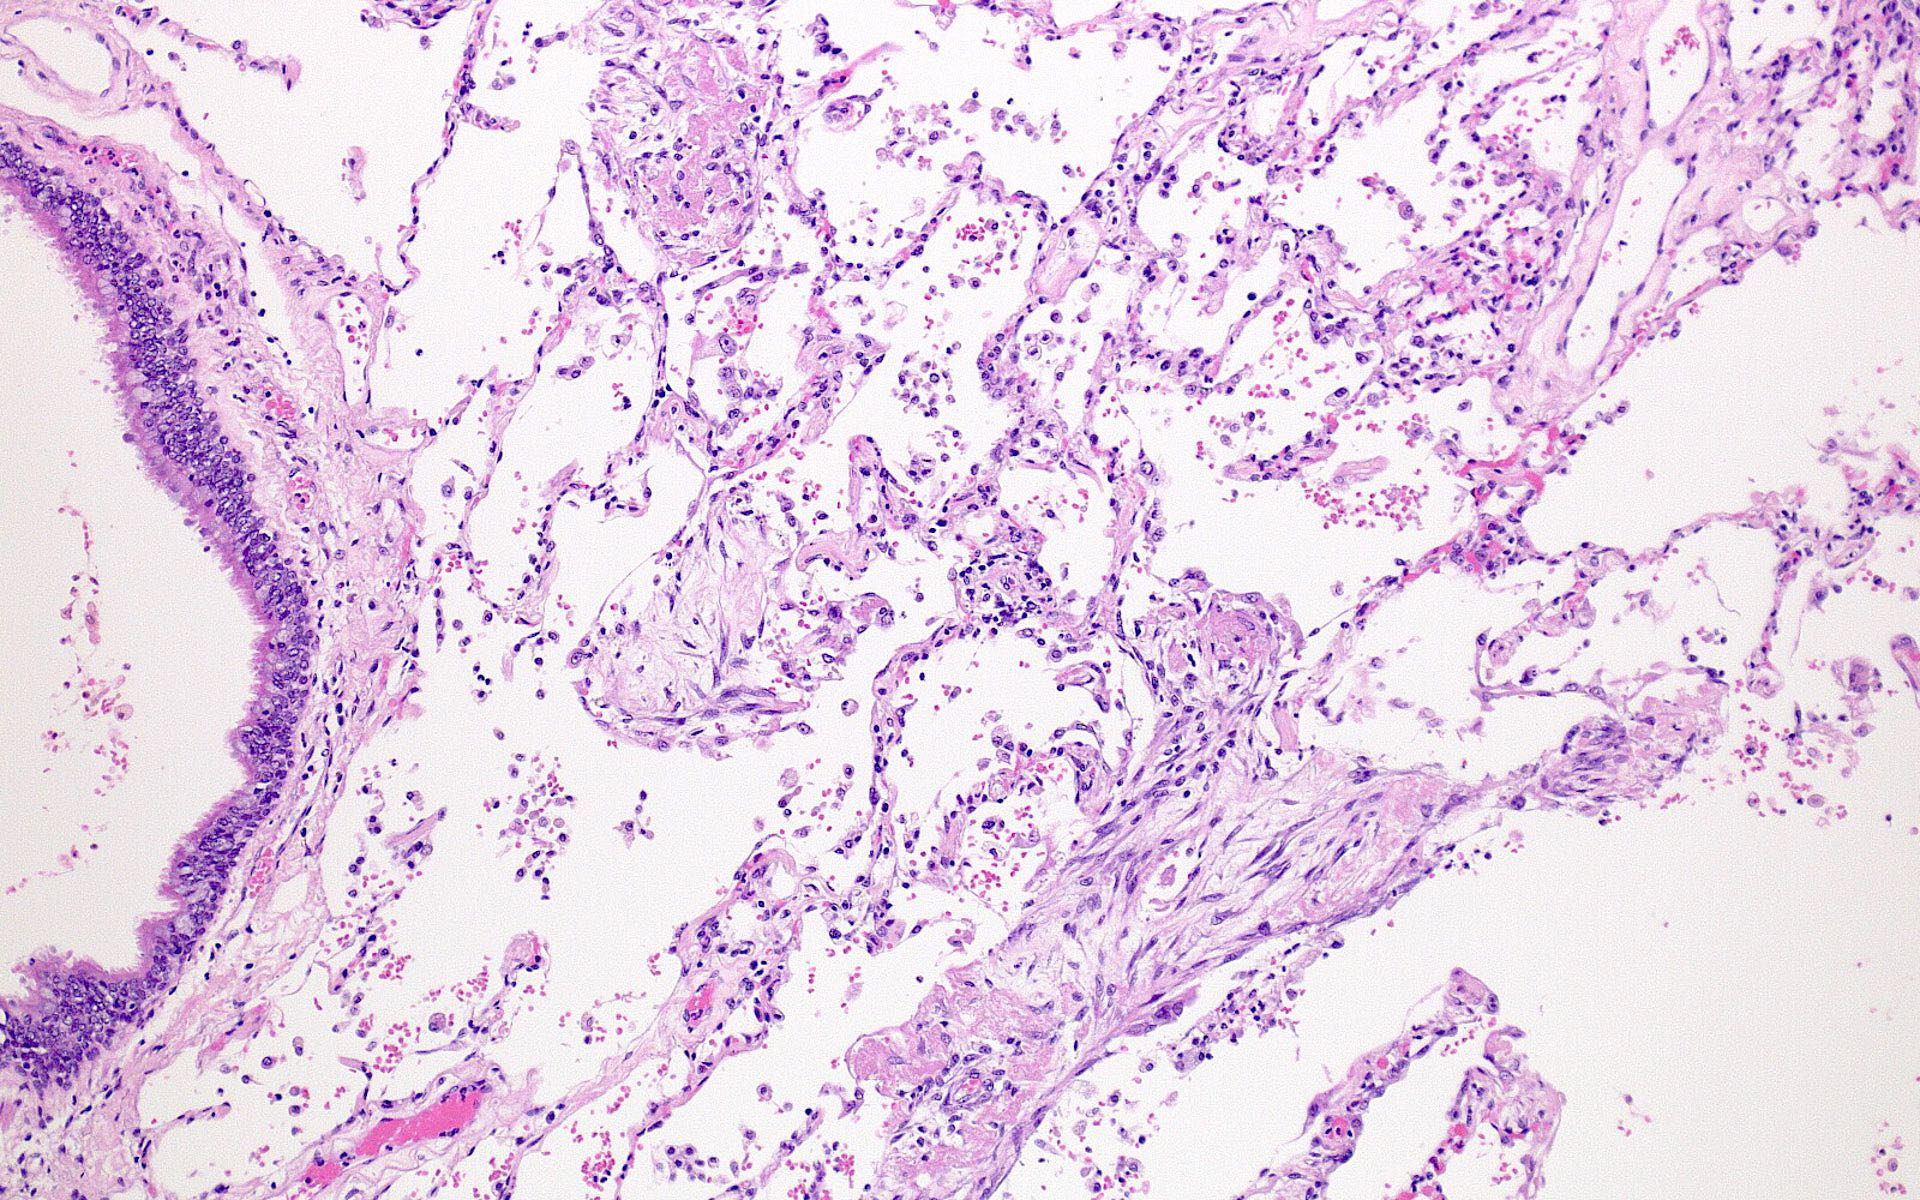

Microscopic (histologic) description

- Histopathology of DAD progresses from exudative (acute) phase through proliferative / organizing (subacute) phase to chronic fibrotic phase roughly corresponding to the period of ARDS (Am J Pathol 1976;85:209, Arch Pathol Lab Med 2010;134:719, Clin Chest Med 2000;21:435, N Engl J Med 2000;342:1334)

- Proliferative / organizing (subacute) phase

- Alveolar change

- Remnants of hyaline membrane with or without organization

- Interstitial and intra-alveolar proliferation of myofibroblasts

- Lymphocytic infiltration

- Epithelial change

- Proliferation / hyperplasia of type II pneumocytes

- Vascular change

- Endothelial injury and thromboemboli in arterioles

- Alveolar change

Microscopic (histologic) images

Contributed by Akira Yoshikawa, M.D. and Yale Rosen, M.D.